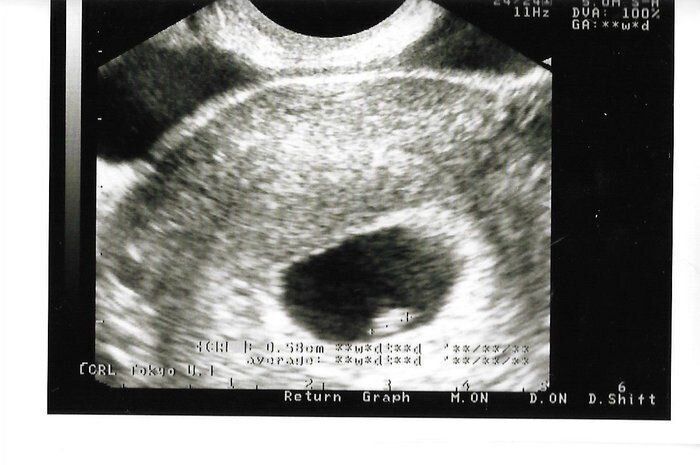

ちゃじゅびさんの妊娠6週目のエコー写真 胎芽が見える

胎嚢が大きくなり、そのなかに胎芽(7週未満の赤ちゃん)が確認できるようになりました。